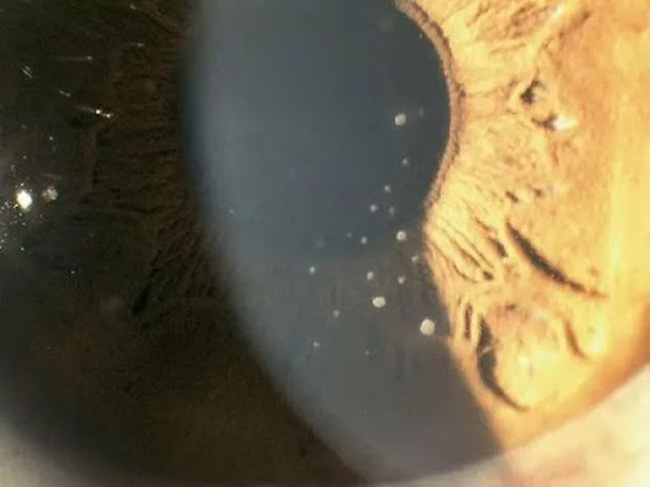

Bác sĩ kiểm tra cho Tiểu Khiết phát hiện IOP (áp lực nội nhãn) ở mắt phải của cô cao tới 55mmHg (IOP bình thường là 10-21mmhg), kết mạc của mắt phải xung huyết nhẹ, phù nề biểu mô giác mạc, và một số cặn lắng được nhìn thấy ở phía sau giác mạc, Tiểu Khiết được chẩn đoán là bệnh tăng nhãn áp.